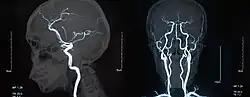

Magnetic resonance imaging

Magnetic resonance imaging (MRI) is a common form of biological data visualization used to form pictures of internal biological processes. Different settings of radiofrequency pulses and gradients result in different image appearances; these combinations are known as MRI sequences. A particularly notable subset of MRI is magnetic resonance angiography, which is a group of techniques used to image arteries and veins. MRI's imaging utility is further expanded upon by diffusion MRI and functional MRI, which can be used to capture neuronal tracts and blood flow respectively.

Diffusion MRI further relies on diffusion tensor imaging (DTI), which measures water molecule diffusion and directionality, and diffusion basis spectrum imaging (DBSI), which extracts multiple anisotropic and isotropic diffusion tensors.[39][40] Functional MRI relies on blood-oxygen-level dependent (BOLD) contrast, which measures the proportion of oxygenated hemoglobin in specific areas of the brain; this allows it to measure and model brain activity based on blood flow.[41] Further MRI techniques include saturation pulses (used to reduce motion artifacts), gradient echo (such as dynamic contrast enhancement), spin echo, and diffusion weighting (a signal contrast generation method based on differences in Brownian motion).[42][43][44]

MIP imaging is also used with magnetic resonance angiography, and research has indicated that it could feasibly be used with MRI.[53] At least one study has shown that MIP MRI actually significantly outperforms single-slice MRI when used by neural networks to classify lesions based on malignancy.[54]